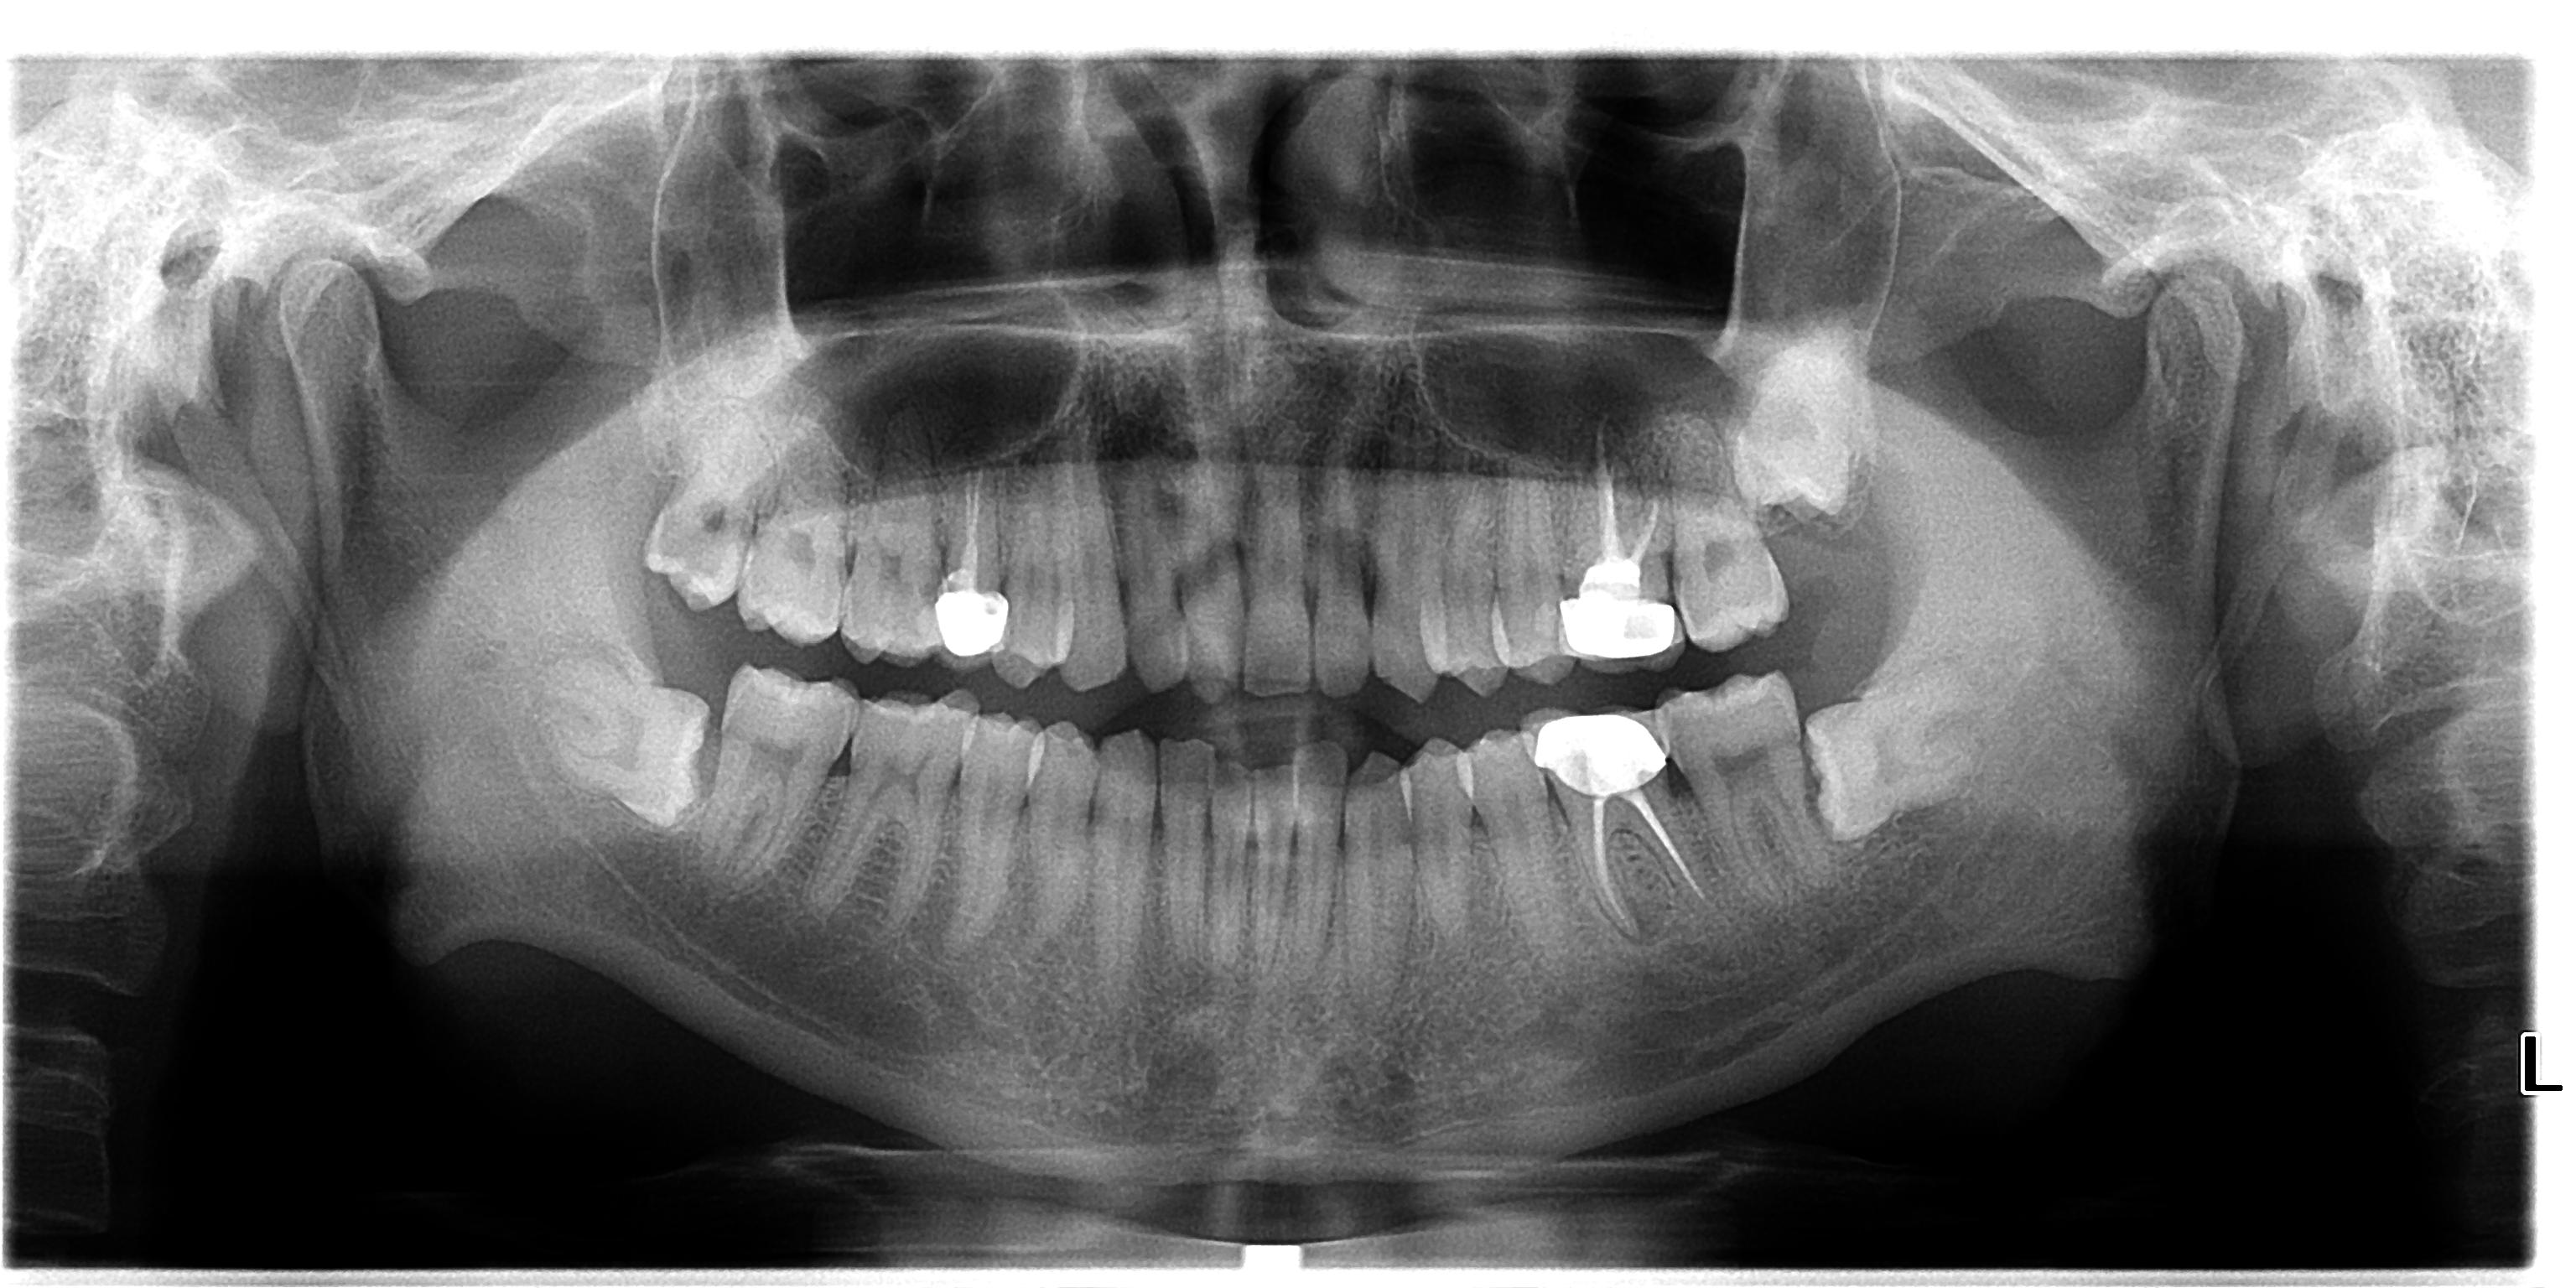

卡瓦口腔全景机价格 (德国卡瓦气动洁牙机)

二手卡瓦单全景机,卡瓦球管、传感器、各个电路板维修更换。